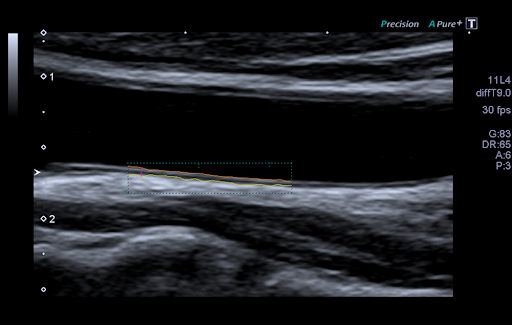

Auto-IMT - это удобный и простой в использовании инструмент для автоматизации измерения толщины интима-медиа (IMT) проксимальных и дистальных стенок артерий. Данная технология незаменима для определения риска сердечно-сосудистых заболеваний у пациента.